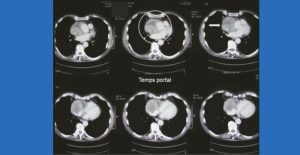

Un cœur bien chaud : que voyez-vous ?

Monsieur M. Robert, âgé de 81 ans, est adressé en consultation pour un tableau évocateur de maladie de Horton un peu atypique. Vous demandez un scanner TAP : comment interprétez-vous…